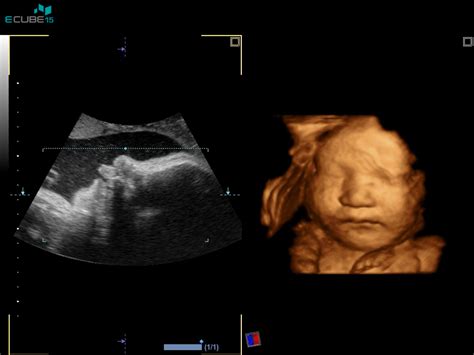

Morfologija ploda je ključni ultrazvočni pregled, ki se običajno opravlja med 20. in 22. tednom nosečnosti. Ta preiskava je namenjena predvsem ugotavljanju morebitnih razvojnih nepravilnosti pri plodu. S pomočjo ultrazvoka ginekolog natančno pregleda vse ključne organe in organske sisteme otroka, vključno s popkovnico. Pregled poteka sistematično, pri čemer se preverjajo različni deli plodovega telesa.

Dodatno se lahko vključi 3D/4D ultrazvok, ki omogoča še natančnejše ocenjevanje razvoja ploda, še posebej srca, okostja in notranjih organov. Ta tehnika je lahko še posebej koristna pri preverjanju sumljivih ultrazvočnih znakov za Downov sindrom, kot so debelina vratne gube, dolžina nosne kosti, prenazalni edem, oblika glavice in razširitev možganskih struktur.